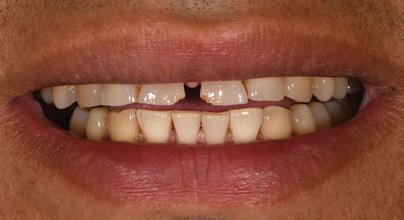

There Is Only One Smile That Matters. Yours!

You are in good hands! Dr. Makarita is the only accredited Fellow of the American Academy of Cosmetic Dentistry in Virginia.

BEFORE AFTER

At Tysons Aesthetic Dentistry Dr. Makarita has designed and equipped his practice with your smile in mind. Dedicated care and attention are just the beginning.

As a general dentist with a passion for aesthetic and cosmetic dentistry, whether a simple filling or a smile makeover, Dr. Makarita’s priority is to help you love your smile.

Since earning his doctorate from the Medical College of Virginia, Dr. Makarita has continually upgraded his skills and knowledge with continuing education so he can always bring you the most advanced options for all your dental needs.

Always welcoming new patients! Call 703-532-2020  8150 Leesburg Pike | Suite 503, Vienna VA 22182 www.ilovethatsmile.com

FREE SMILE EVALUATION In person or visit website for virtual smile consultation

Dr. H.R. Makarita

Accredited Fellow, American Academy of Cosmetic Dentistry

Master, Academy of General Dentistry

Master, International Congress of Oral Implantologists

Master, Las Vegas Institute for Advanced Dental Studies

to Love Your Smile? Dr. Makarita would love to meet you! About